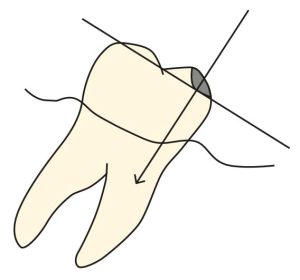

In general, maxillary posterior teeth are tilted in the facial direction and mandibular teeth in the lingual direction, resulting in a change in the contour height of the teeth. To ensure the correct placement of the prosthetic components, the enamel surface is corrected with a beveled cylindrical bur (Figures 10-26 and 10-27).